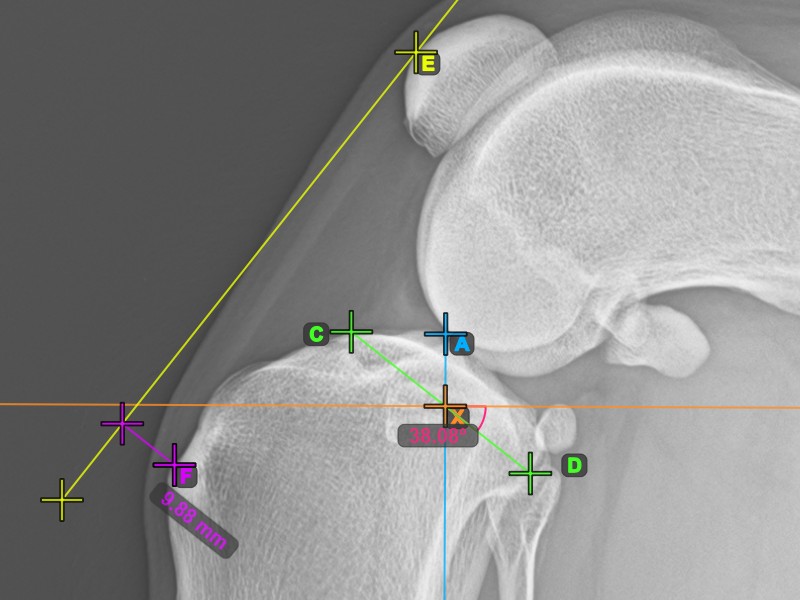

To complete the TTA measurement procedure mark the most dorsal point of the Crista Tibiae (Tuberositas Tibiae). The distance between the Tuberositas Tibiae and the line passing along the most cranial point of the Patella is the required adjustment for the TTA procedure.

The image below depicts the usual placement of the tibial tuberosity, the most prominent point of the tibial crest.

Modify the points constructing the measurement to recalculate the required advancement that should be made during the TTA procedure.